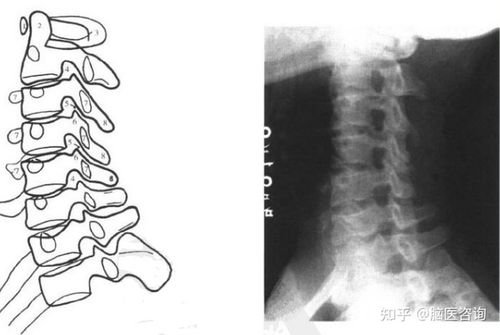

颈椎正侧位不易于观察寰,枢椎情况,通过张口位拍片,可以观察寰,枢椎有

颈椎张口位

二,颈椎张口位片